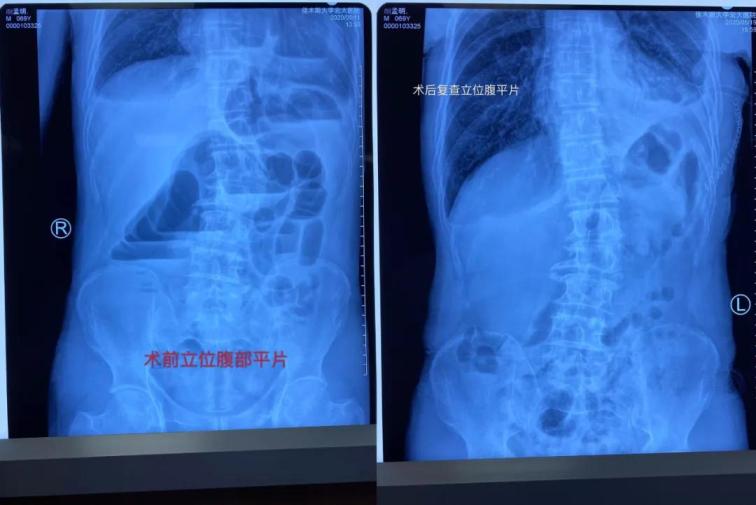

患者顏某某,男,69歲,因“間斷性腹痛腹脹、惡心嘔吐肛門停止排氣排便4天”于5月11日17時(shí)22分經(jīng)門診掛號(hào)診療,以“腸梗阻”收住我院普外一科。主管醫(yī)生張志光詳細(xì)詢問(wèn)患者病史、全面查體,結(jié)合相關(guān)輔助檢查,入院給予禁食水、胃腸減壓和補(bǔ)液治療。

雖然患者表現(xiàn)為腸梗阻癥狀,但是從事普外多年、細(xì)心的張醫(yī)生對(duì)患者的胸部CT心前區(qū)顯示低密度影像產(chǎn)生疑問(wèn),懷疑膈疝可能,并于5月12日晨找胸外科周鋼主任會(huì)診。 周鋼主任結(jié)合病史、癥狀、查體、輔助檢查,高度懷疑膈疝中的心膈角疝,疝內(nèi)容物考慮結(jié)腸可能,因患者目前表現(xiàn)為腸梗阻,腸管卡壓時(shí)間長(zhǎng)易導(dǎo)致壞死,且胸部CT表現(xiàn)心包填塞,此時(shí)動(dòng)脈血壓已經(jīng)下降,靜脈血壓升高,脈壓差縮小,已經(jīng)出現(xiàn)休克。

術(shù)中發(fā)現(xiàn)橫結(jié)腸疝入心包并嵌頓,腸管高度擴(kuò)張,已經(jīng)顏色較暗,同時(shí)疝入心包腔內(nèi)還有大網(wǎng)膜,已表現(xiàn)血運(yùn)障礙。心臟嚴(yán)重受壓,近乎停止跳動(dòng)。緊急切開(kāi)擴(kuò)大疝環(huán),觀察疝入的腸管和大網(wǎng)膜血運(yùn)情況,約觀察30分鐘血運(yùn)障礙恢復(fù)后,小心將疝入的腸管和大網(wǎng)膜還納入腹腔。心包腔恢復(fù)原有空間,心臟開(kāi)始恢復(fù)節(jié)律性跳動(dòng)。術(shù)后病人轉(zhuǎn)入胸外科病房,監(jiān)護(hù)綜合治療護(hù)理,目前患者恢復(fù)良好。